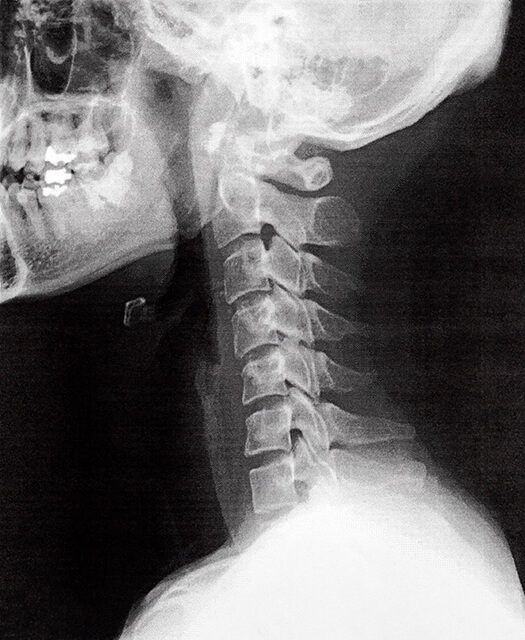

そうすると、緩やかなカーブを描いているのが正常な首の状態がまっすぐに…。

めまいの原因となる、ストレートネックと言われる現代病ともいえる症状になります。

つまり正常な姿勢であれば、体はきれいなS字カーブを描いているのですが、ストレートネックであればS字カーブは描かれていません。

首が前傾で突き出たような状態であり、その状態で首はまっすぐになっているのがストレートネックです。